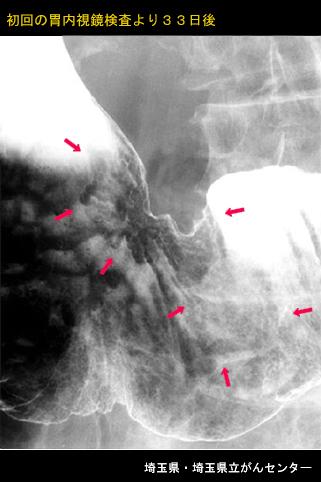

Posted by: Saitama Pref., 琦玉县立癌中心 (Dr.多田等)

疾病(病理主体)的分类恶性上皮性肿瘤/腺癌

部位(按器官分)胃(部位)/2个以上

检查方法X线

肿瘤的肉眼分类0型(表在型)/IIc型(IIc+IIa)

肿瘤最大直径40以上

肿瘤的深度sm

多发性肿瘤(同一器官)有(同时性)